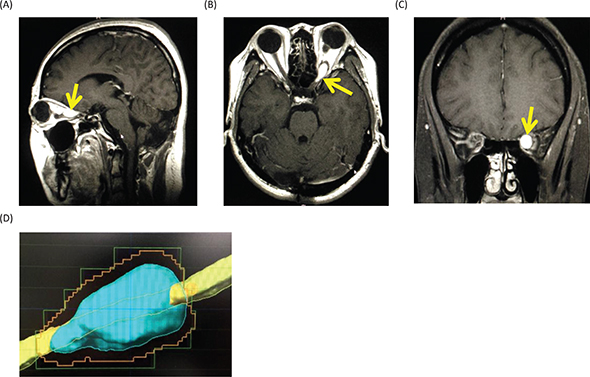

Magnetic resonance imaging (MRI) of the head showed a Gd-enhanced well-circumscribed mass on the left retrobulbar optic nerve in the orbital, and three-dimensional MRI showed the tumor enveloped the left optic nerve (Figure 4).

Figure 4. Magnetic resonance images before radiosurgery. (A) Gadolinium (Gd)-enhanced T1-weighted image, sagittal. (B) Gd-enhanced T1-weighted image, axial. (C) Gd-enhanced T1-weighted image, coronal. Yellow arrows show the tumor. (D) Three-dimensional planning MRI for radiosurgery. The light blue color indicates the tumor enveloping the optic nerve.

The differential diagnoses for the tumor include optic glioma, optic sheath meningioma, optic nerve schwannoma and optic nerve hemangioblastoma. Among them, since the patient is a VHL patient, the most probable diagnosis was thought to be an optic nerve hemangioblastoma. Therefore, we made a decision to treat the tumor with stereotactic radiosurgery. At Shonan Fujisawa Tokushukai Hospital, the stereotactic radiosurgery was prescribed with the dose being 39 Gy/13 fractions using Novalis. The planning target volume was set at 0.7 mL, and D95 (95% of standard irradiation volume) was set at 35 Gy/13 fractions. The patient completely lost her vision after the radiosurgery. Eighteen months after the radiosurgery, the tumor volume slightly decreased (Figure 5), but her vision has been still lost. The consent to publish the case has been given by the patient.

Figure 5. Gadolinium-enhanced magnetic resonance images at 18 months after the stereotactic radiosurgery. (A) Sagittal image. (B) Axial image. (C) Coronal image.